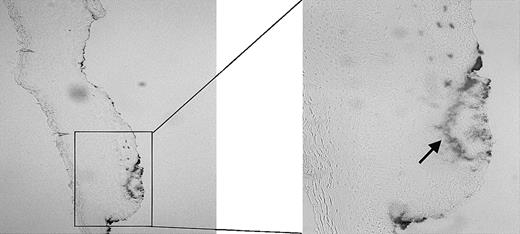

Using the wound-healing model as described in “Materials and methods,” we first examined the effect of injury on heme release using benzidine staining. As demonstrated in Figure 2, large amounts of free heme/hemoproteins are visible at the site of injury, whereas in the surrounding noninjured tissue no heme can be detected.

Presence of heme. The presence of heme in a fresh wound of a Wistar rat was analyzed using benzidine staining. The heme (arrow) has clearly accumulated at the sites of injury. Original magnification, × 100 (left panel) and × 265 (right panel).